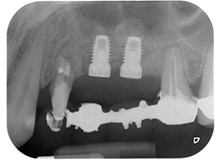

Fig. 1 : Patiente de 58 ans. Radio pré-opératoire montrant une lésion du parodonte apical à la dent 24 et une perte horizontale d'os alvéolaire dans le deuxième quadrant.

Une patiente de 58 ans se plaignait de douleurs et d'une mobilité accrue de la dent pilier 24 de son bridge. Présence d'une inflammation parodontale avec formation de poches de 7 mm de profondeur dans le sens mésiobuccal et de plus de 12 mm dans le sens distal, ainsi que d'une atteinte de la furcation au troisième degré. La radiographie a par ailleurs révélé une lésion parodontale étendue autour de la région apicale de la dent 24 ayant préalablement reçu un traitement endodontique (alio loco) (Fig. 1).

Un an plus tôt, les dents 25 et 26 avaient été extraites à la suite d'un traumatisme et pour cause d'atteinte endo-parodontale, avant la pose du bridge. Une lésion endo-parodontale combinée a été diagnostiquée pour la dent 24, d'étiologie incertaine. La patiente voulait conserver ses dents piliers 24 et 27 et refusait toute prothèse amovible à titre définitif, et même provisoire. Par conséquent, malgré un pronostic défavorable compte tenu des résultats des radios et des examens cliniques, il a été convenu de faire le maximum pour conserver les deux dents.

La pose de deux implants submergés a été programmée sur les sites 25 et 26, lors d'une intervention chirurgicale incluant un débridement parodontal ouvert et une apicectomie de la dent 24. Du fait du défaut osseux vertical sur le site d'implantation futur, une élévation sinusienne par voie interne a également été programmée.

Fig. 16 : Radiographie postopératoire montrant les implants en place, avec le substitut osseux de l'élévation sinusienne interne autour des apex. On observe autour des racines de la dent 24 du matériau provenant de la procédure de GTR.